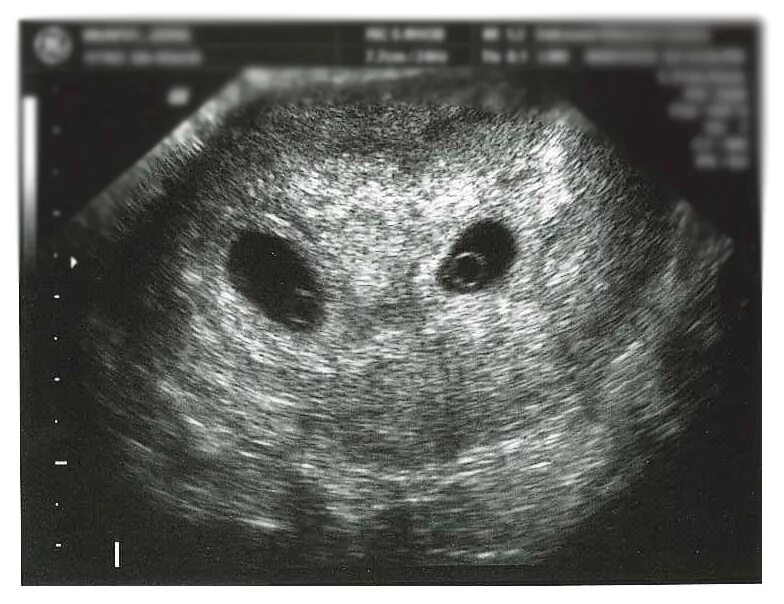

Беременность по узи 4 5